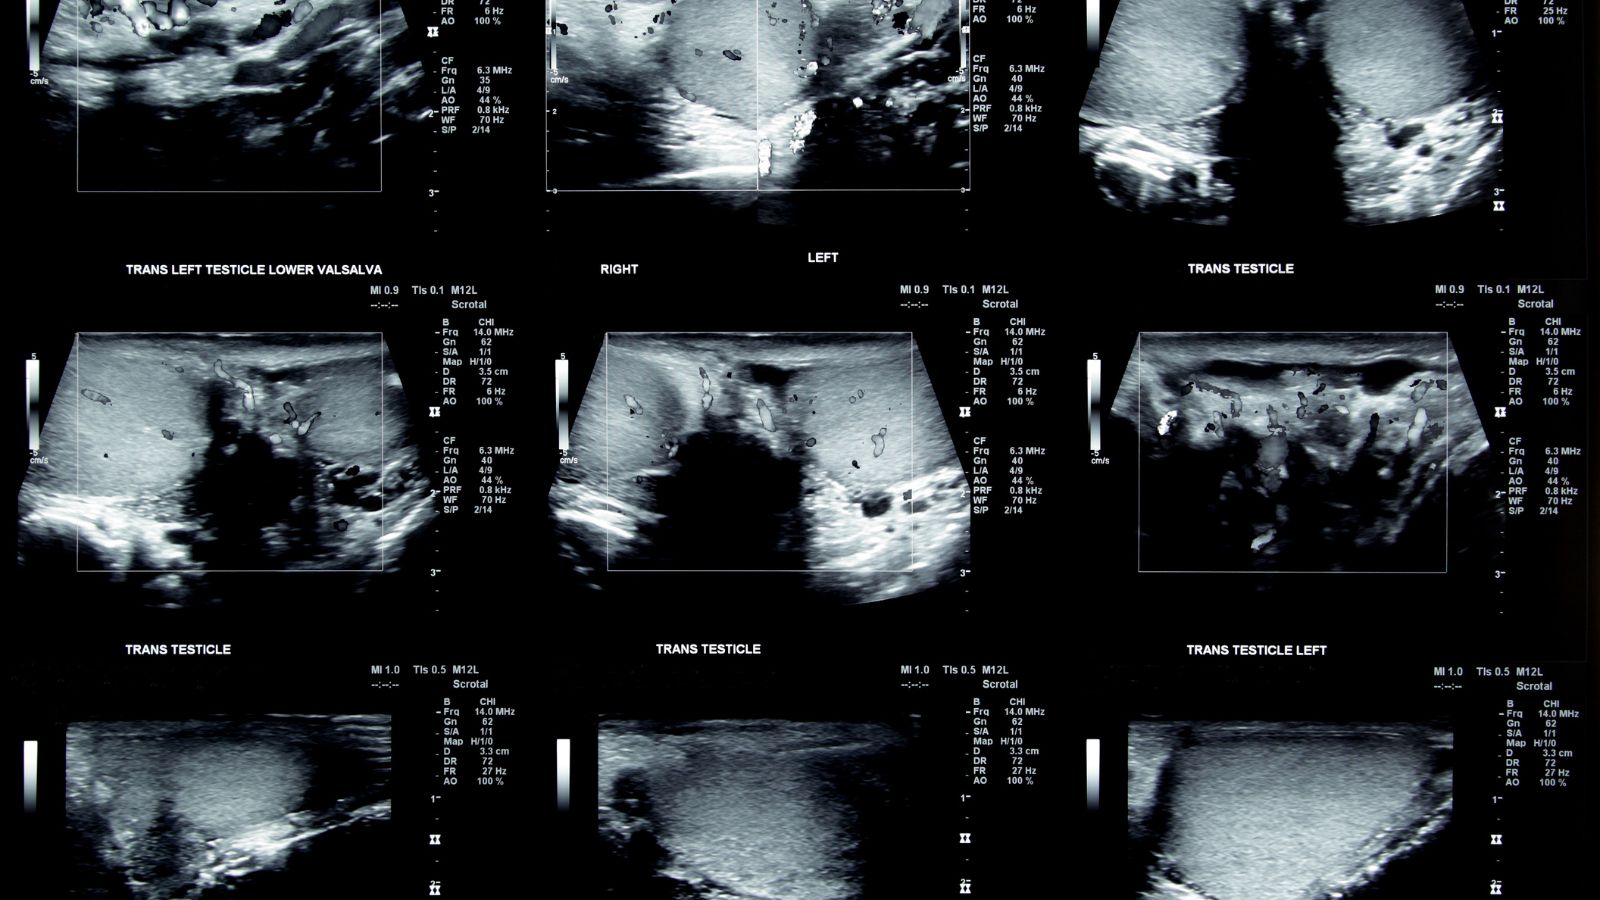

Siêu âm tinh hoàn là một phương pháp chẩn đoán hình ảnh không xâm lấn, sử dụng sóng âm tần số cao để tạo ra hình ảnh chi tiết của tinh hoàn và các cấu trúc xung quanh. Phương pháp này giúp bác sĩ kiểm tra và phát hiện các bất thường như khối u, viêm, giãn tĩnh mạch thừng tinh, xoắn tinh hoàn, hoặc các vấn đề liên quan đến sức khỏe sinh sản nam giới. Siêu âm tinh hoàn rất an toàn, không gây đau và không yêu cầu sử dụng tia X, giúp theo dõi tình trạng sức khỏe của tinh hoàn một cách hiệu quả.

- Xoắn tinh hoàn: Siêu âm Doppler giúp phát hiện sự tắc nghẽn mạch máu và dòng máu lưu thông không đều, một dấu hiệu của xoắn tinh hoàn. Đây là một tình trạng cấp cứu và siêu âm giúp chẩn đoán nhanh chóng.

- Thực hiện siêu âm: Bác sĩ sẽ di chuyển đầu dò siêu âm trên vùng bìu, tạo ra hình ảnh của tinh hoàn trên màn hình. Quá trình này không gây đau, chỉ có thể cảm thấy hơi khó chịu khi đầu dò di chuyển.

- Đánh giá kết quả: Bác sĩ sẽ xem xét các hình ảnh và đưa ra kết luận về tình trạng tinh hoàn. Nếu cần thiết, bác sĩ sẽ đề xuất các xét nghiệm hoặc điều trị tiếp theo.